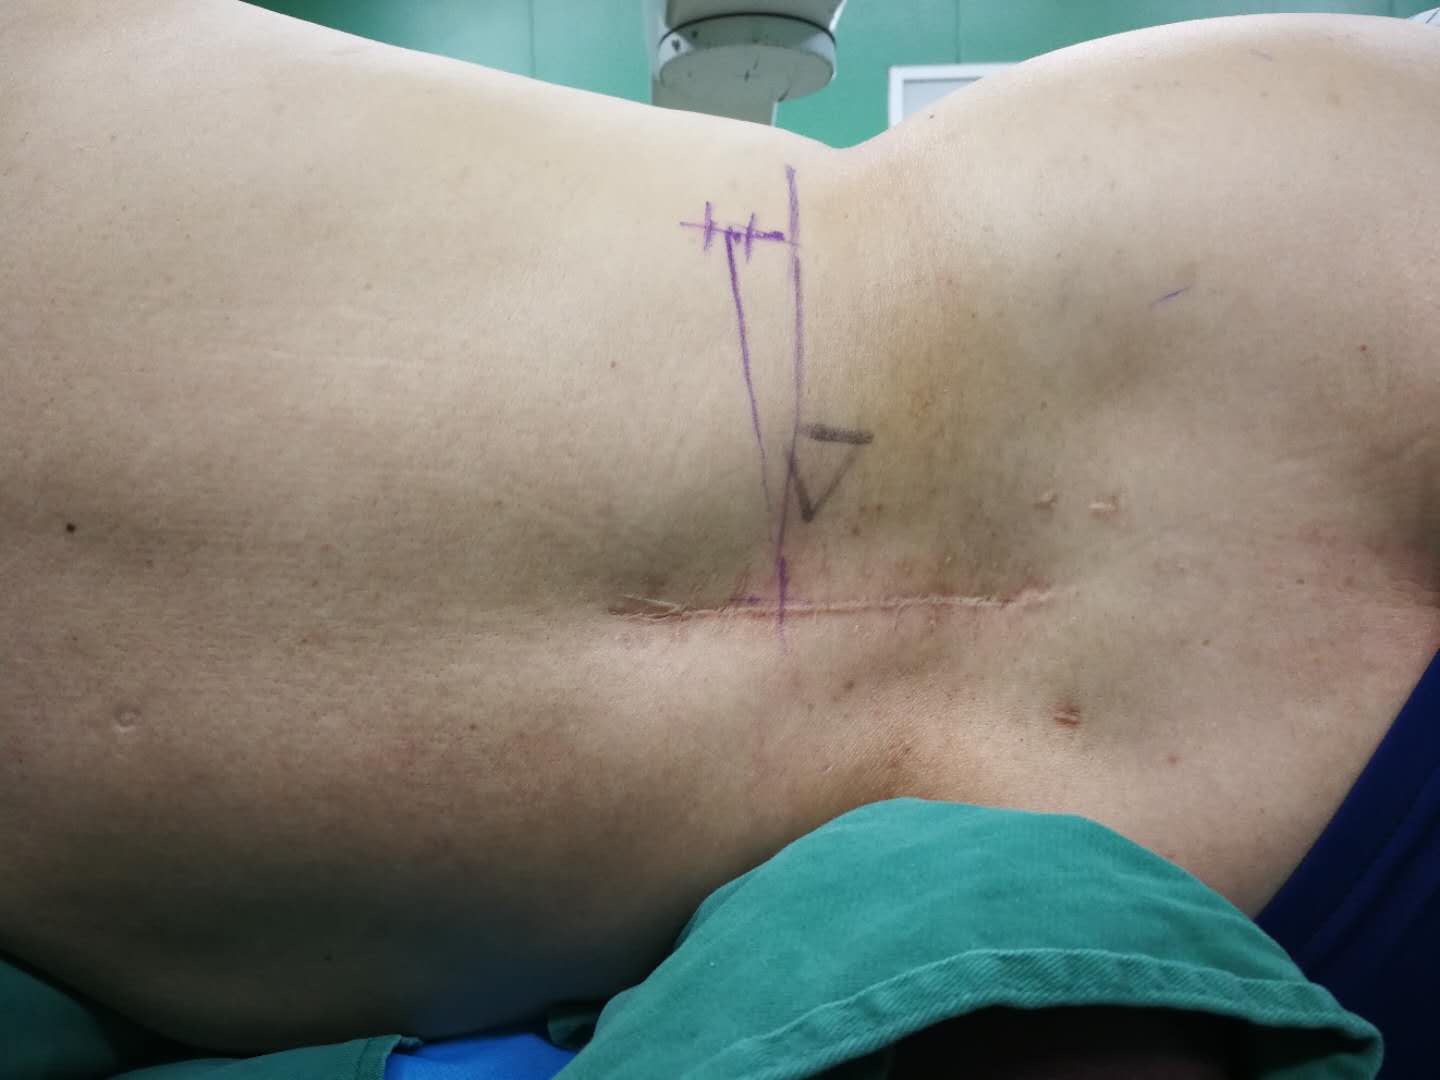

12月30日,我院骨五科医疗团队成功完成一例经皮椎间孔镜上腰椎极外侧间盘突出切除术。这一手术的成功开展,标志着我院在脊柱外科领域的微创治疗技术又上了一个新台阶。 患者高先生8年前曾因下腰椎腰4-腰5、腰5-骶1椎间盘突出,于我院骨五科行腰4-腰5、腰5-骶1椎板减压+椎间盘切除+椎间植骨融合术,为其解除了病痛。4年前患者行腰椎内固定取出术。半年前患者无明显原因再次出现腰部疼痛,咳嗽时尤为明显,遂再次求诊与我科。我院骨五科主任钱宏主任医师组织科室医疗团队,经过对患者的详细查体和相关影像学检查,诊断为由腰椎融合术后退变引起的上腰椎(腰2)极外侧间盘突出症,突出的椎间盘压迫出口神经根,导致患者再次出现腰部和腿部疼痛。 考虑到高先生既往曾经历过两次传统脊柱切开手术,如果再次运用该手术来切除突出的椎间盘,对其自身的脊柱解剖结构损伤比较大,会影响到脊柱的稳定性,日后的生活质量也会受到较大的影响。我院骨五科主任钱宏主任医师组织科室医疗团队,多次讨论手术方案、反复评估手术效果,最终决定为高先生实施经皮椎间孔镜上腰椎极外侧间盘突出切除术。 在征得高先生及其家属的同意后,钱宏主任带领科室医疗团队成员高炬、朱步奇、王海蛟医师,在局麻下利用穿刺针,经病变椎体后外侧穿刺至椎间孔处,在扩大椎间孔及神经根管后,建立了手术微创通道,并通过该通道对其突出的椎间盘实施了切除。 术后,高先生的恢复状况良好,腰间也仅留下了一个1厘米左右的伤口,“手术过程中,我就明显感觉自己的症状在减轻,腿也不那么麻了。术后第2天,就可以下床行走,还能自己去上厕所。”高先生满意地介绍说。 经皮椎间孔镜技术,是脊柱外科领域典型的微创手术,相对于传统的脊柱切开手术,该手术切口小,对患者脊柱的解剖结构基本上无损伤,最大程度地保护了脊柱后方软组织,还大大减少了医源性并发症的发生,提高了手术的安全性。患者术后康复时间短,基本不影响其的日常生活。据介绍,该技术还能应用于部分颈椎间盘突出疾病的治疗,为更多的患者带来了健康的福音。 我院骨五科主任钱宏主任医师组织其科室医疗团队成员高炬、朱步奇、王海蛟医师,前往中国人民解放军总医院(301医院)、北京积水潭医院等地进修学习,现已熟练掌握了该项技术,目前已成功开展多例该项手术,为患者解除了病痛。

体表定位 术中操作